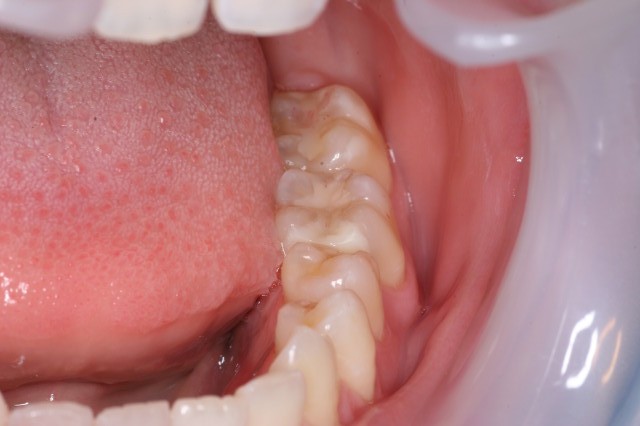

外傷の症例です

転んで前歯を打った小児です

左上の前歯がぶつけた事で少し内側に曲がっていました。

曲がった歯を元の位置に戻して噛んだ時にいたくないように接着剤とハリガネを使って固定します

固定期間は2〜4週間です。

固定期間中も普通に生活する事が出来ます。もちろん治療は保険診療です

完全に「歯が抜けた」としてもかなりの確率でくっつきます(私の臨床経験ではほとんど100%)ので諦めずに抜けた歯は必ず持ってきて下さい

下の写真では転んで前歯が完全に抜けてしまった症例です。

道に左上の一番手前の歯は落ちていました、歯を支えている骨も骨折しており口の中も2針、唇も3針縫っています。

もちろん歯が抜けているのでハリガネと接着剤でとめています。4週間の固定で歯は完全にくっつきました、唇の傷も治って今では何もなかったかのようにキレイになっています。

ぶつけて歯が抜けても焦らず見つけて出来るだけ早く受診して下さい。 |